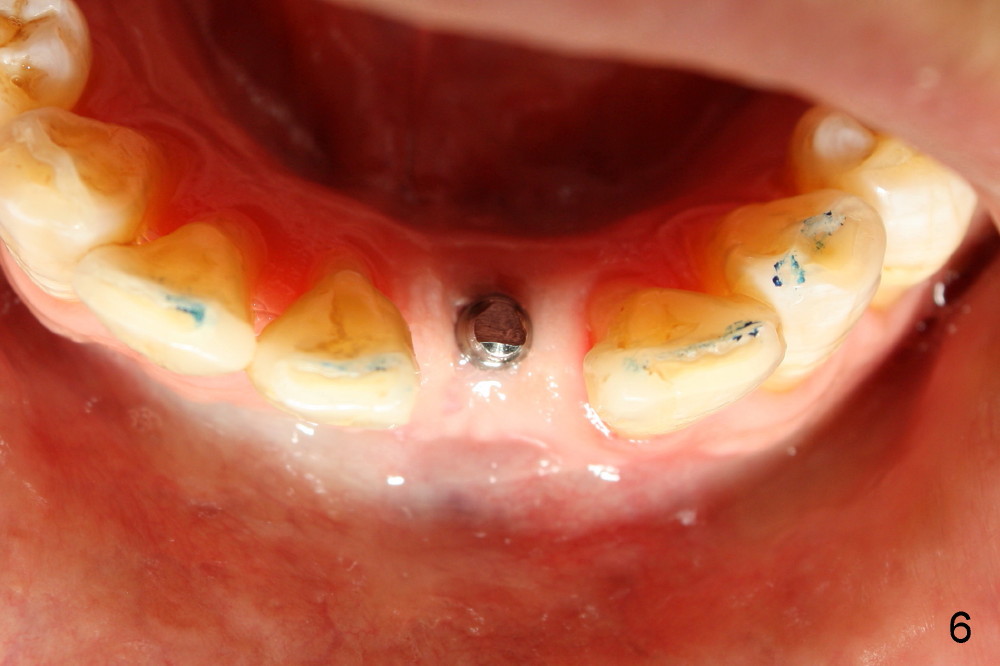

A 3x17 mm one piece implant is planned. Osteotomy is created by a 1.5 mm pilot drill at the depth of 14 mm without incision (Fig.2); it is close to a neighboring incisor. The trajectory of the osteotomy is intended to be changed (Fig.3 red) without success (white, 17 mm deep). With measurement and calculation, the 3x17 mm implant is not expected to touch the root of the adjoining tooth. In fact it is fine with insertion torque between 50-60 Ncm (Fig.4). Without incision, the papillae appear to form immediately following implantation (Fig.5). With adjustment of the abutment (Fig.6), an immediate provisional is fabricated (Fig.7).

Fig.10,11 show 7 day follow up. The permanent crown is seated 4.5 months postop (Fig.12). Minimal bone resorption occurs at the crest 4 months postop (Fig.13), which is most likely associated with conservative approach (flapless). The patient returns for follow up 2.5 months post cementation (Fig.14,15). The implant remains in the bone 4 years post cementation (Fig.16 CT coronal section; lingual thread exposure, corresponding to preop defect in Fig.1). There is mild coronal bone resorption 5 years 4 months post cementation (Fig.17).